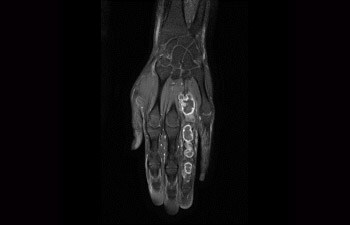

A revolutionary breakthrough in diagnostic quality – and speed

3.0T imaging at your fingertips

Enhanced diagnostic confidence in neuro oncology